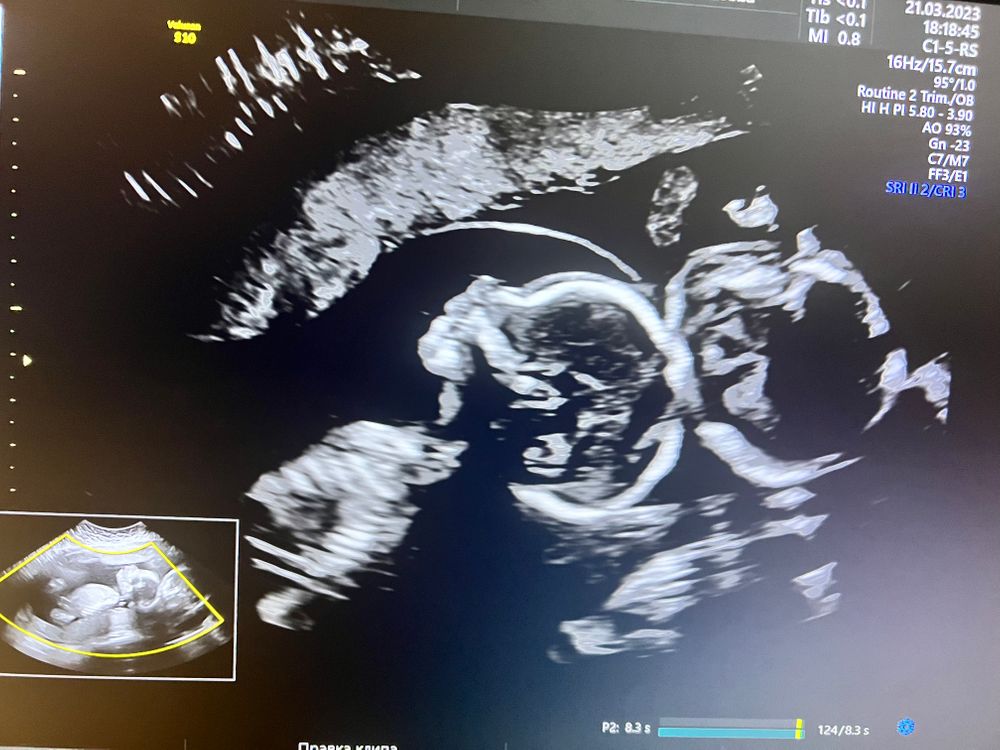

Второй скрининг 🙈

Мои пирожочки сегодня ездили на второй скрининг, врач Узи назвала их синхронистами - лежат прям как батона , головами вниз и синхронно ) намерили все как положено . Я, конечно ж , опять пустила скупую женскую слезу когда включили сердцебиения . Дама отворачивалась и меня отправили погулять , что б глянуть лицо и там все. После половины стаканчика кока-колы стала очень сговорчивой и устроила просто дикие танцы , все удалось померить и разглядеть .

мальчуган 295 г, девочка 275 г.

А на втором снимке они не головенками друг к другу?) а то у меня один товарищ уверенно так другого по черепушке ногами дубасил)